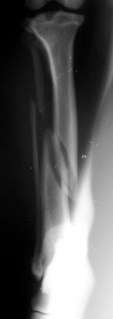

Προσθoπίσθια ακτινογραφία κνήμης σκύλου: λοξό κάταγμα μεσότητας διάφυσης κνήμης - περόνης

Προσθoπίσθια ακτινογραφία κνήμης:

λοξό κάταγμα μεσότητας

διάφυσης κνήμης – περόνης.